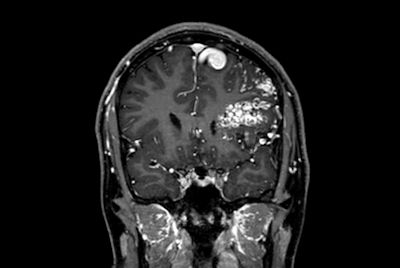

Brain with multiple lesions